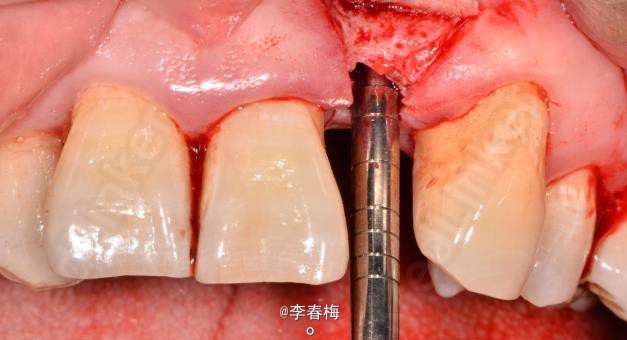

上颌前牙种植修复

患者,男,左上颌侧切牙缺失来诊。平素体质一般,无药物、食物过敏史,无高血压、心脏病等系统性疾病。